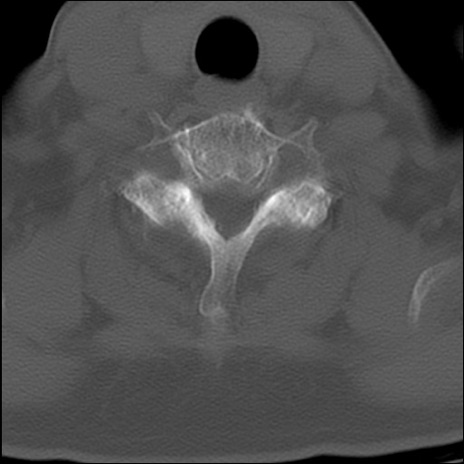

症例48 頚椎CT(横断像)

頚椎CT